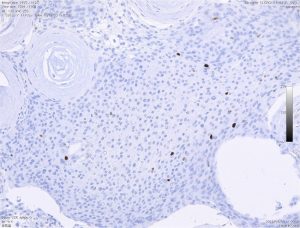

meningothelial meningioma : collagen ball コラーゲン・ボール

whorl patternが変性すると,無機質な構造へと変化します。meningothelial meningiomaの一部像として重要な所見です。これはとてもゆっくり増大する良性の髄膜腫の特徴でもあります。下の右側のMIB-1(Ki-67)染色では1%くらいが陽性で低値と言えます。